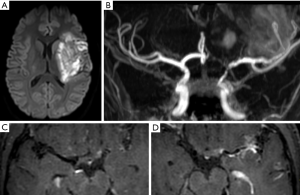

However, although thinner, intracranial vessels have already been studied with post gadolinium VW MRI in more than 20 studies and several meta-analyses (13,14,19,20) focused on the determination of markers of intracranial culprit plaque. These studies typically exclude other causes of stroke, such as atrial fibrillation, severe cervical carotid stenosis, or vasculitis. The main VW MRI findings of ICAD plaque are eccentric enhancement of the plaque with a variable length of involvement remaining most frequently focal (11,15,21). In patients with recent stroke, multiple studies have reported an association between T1 post-contrast plaque enhancement and the symptomatic status of the ICAD plaque (Figure 1).

Lee et al. (14) reported that intracranial plaque with contrast enhancement, positive remodeling, and wall irregularity were significantly more likely to be associated with ischemic stroke at the corresponding territory. On a meta-analysis, using a random effects model, Gupta et al. (19) reported that infarction was 10 times more likely in tissue supplied by an enhancing artery than in tissue supplied by nonenhancing arteries. Overall in their study, 59% of the culprit plaques were enhancing versus 23% of the non-culprit plaques.

Quantitative analysis (22) of the enhancement, comparing pre and post-contrast intensity values of the ICAD plaque, support this hypothesis and found that the percentage increase in enhancement after contrast was significantly higher for symptomatic plaques (63 vs. 23%, P=0.001). An analysis of different plaque features found that high signal on T1-weighted images, wall thickening pattern, and a high degree of postcontrast enhancement were associated with culprit plaque (23).